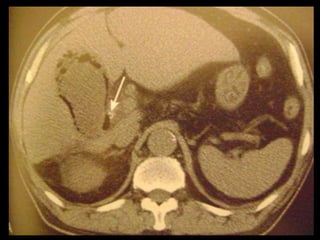

Colecistite aguda

Achados na TC: cálculos biliares, espessamento da

parede, alterações inflamatórias

perivesiculares, bile com alta

atenuação, borramento da interface VB-fígado e

aumento transitório da atenuação do fígado

perivesicular;

http://radiographics.rsna.org/content/28/1/135.full